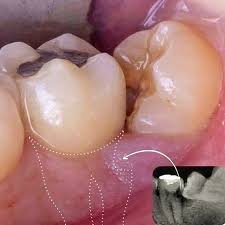

Desgaste o daño al diente de al lado

Por estas razones, es fundamental realizar una evaluación radiográfica y un diagnóstico oportuno.